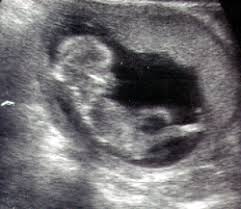

تلقى مأمور مركز شرطة القوصيه بلاغا من المستشفى المركزي بوصول منى سيد محمد 25 سنه ربه منزل ومقيمه بالقوصيه فى

حالة إجهاض لحمل عمر ثلاثة أشهر وتم إجراء عملية تفريغ لها